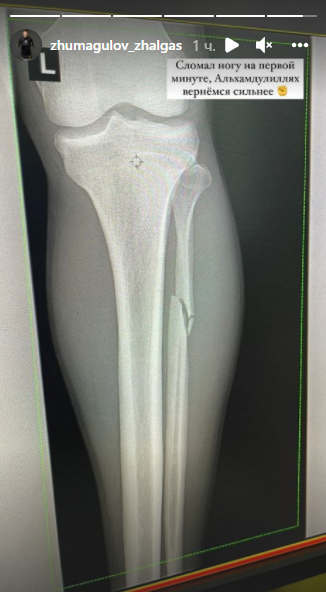

Жалгас Жумагулов сломал ногу на первой минуте боя, в котором его отправили в нокаут

Казахстанский боец Жалгас Жумагулов в сториз в Instagram рассказал о травме, которую получил в предыдущем бою в UFC, передаёт медиа-портал Сaravan.kz.

Казахстанец признался, что провёл четвёртый бой в UFC с серьёзным повреждением ноги. Он выложил фотографию рентгена, которую подписал: "Сломал ногу на первой минуте, Альхамдулиллях, вернёмся сильнее".

Напомним, 5 декабря Жалгас Жумагулов отправился в нокаут после первого раунда в бою, рассчитанном на три. В его четвёртом выступлении на турнире UFC казахстанец проиграл ангольцу Манела Капа.